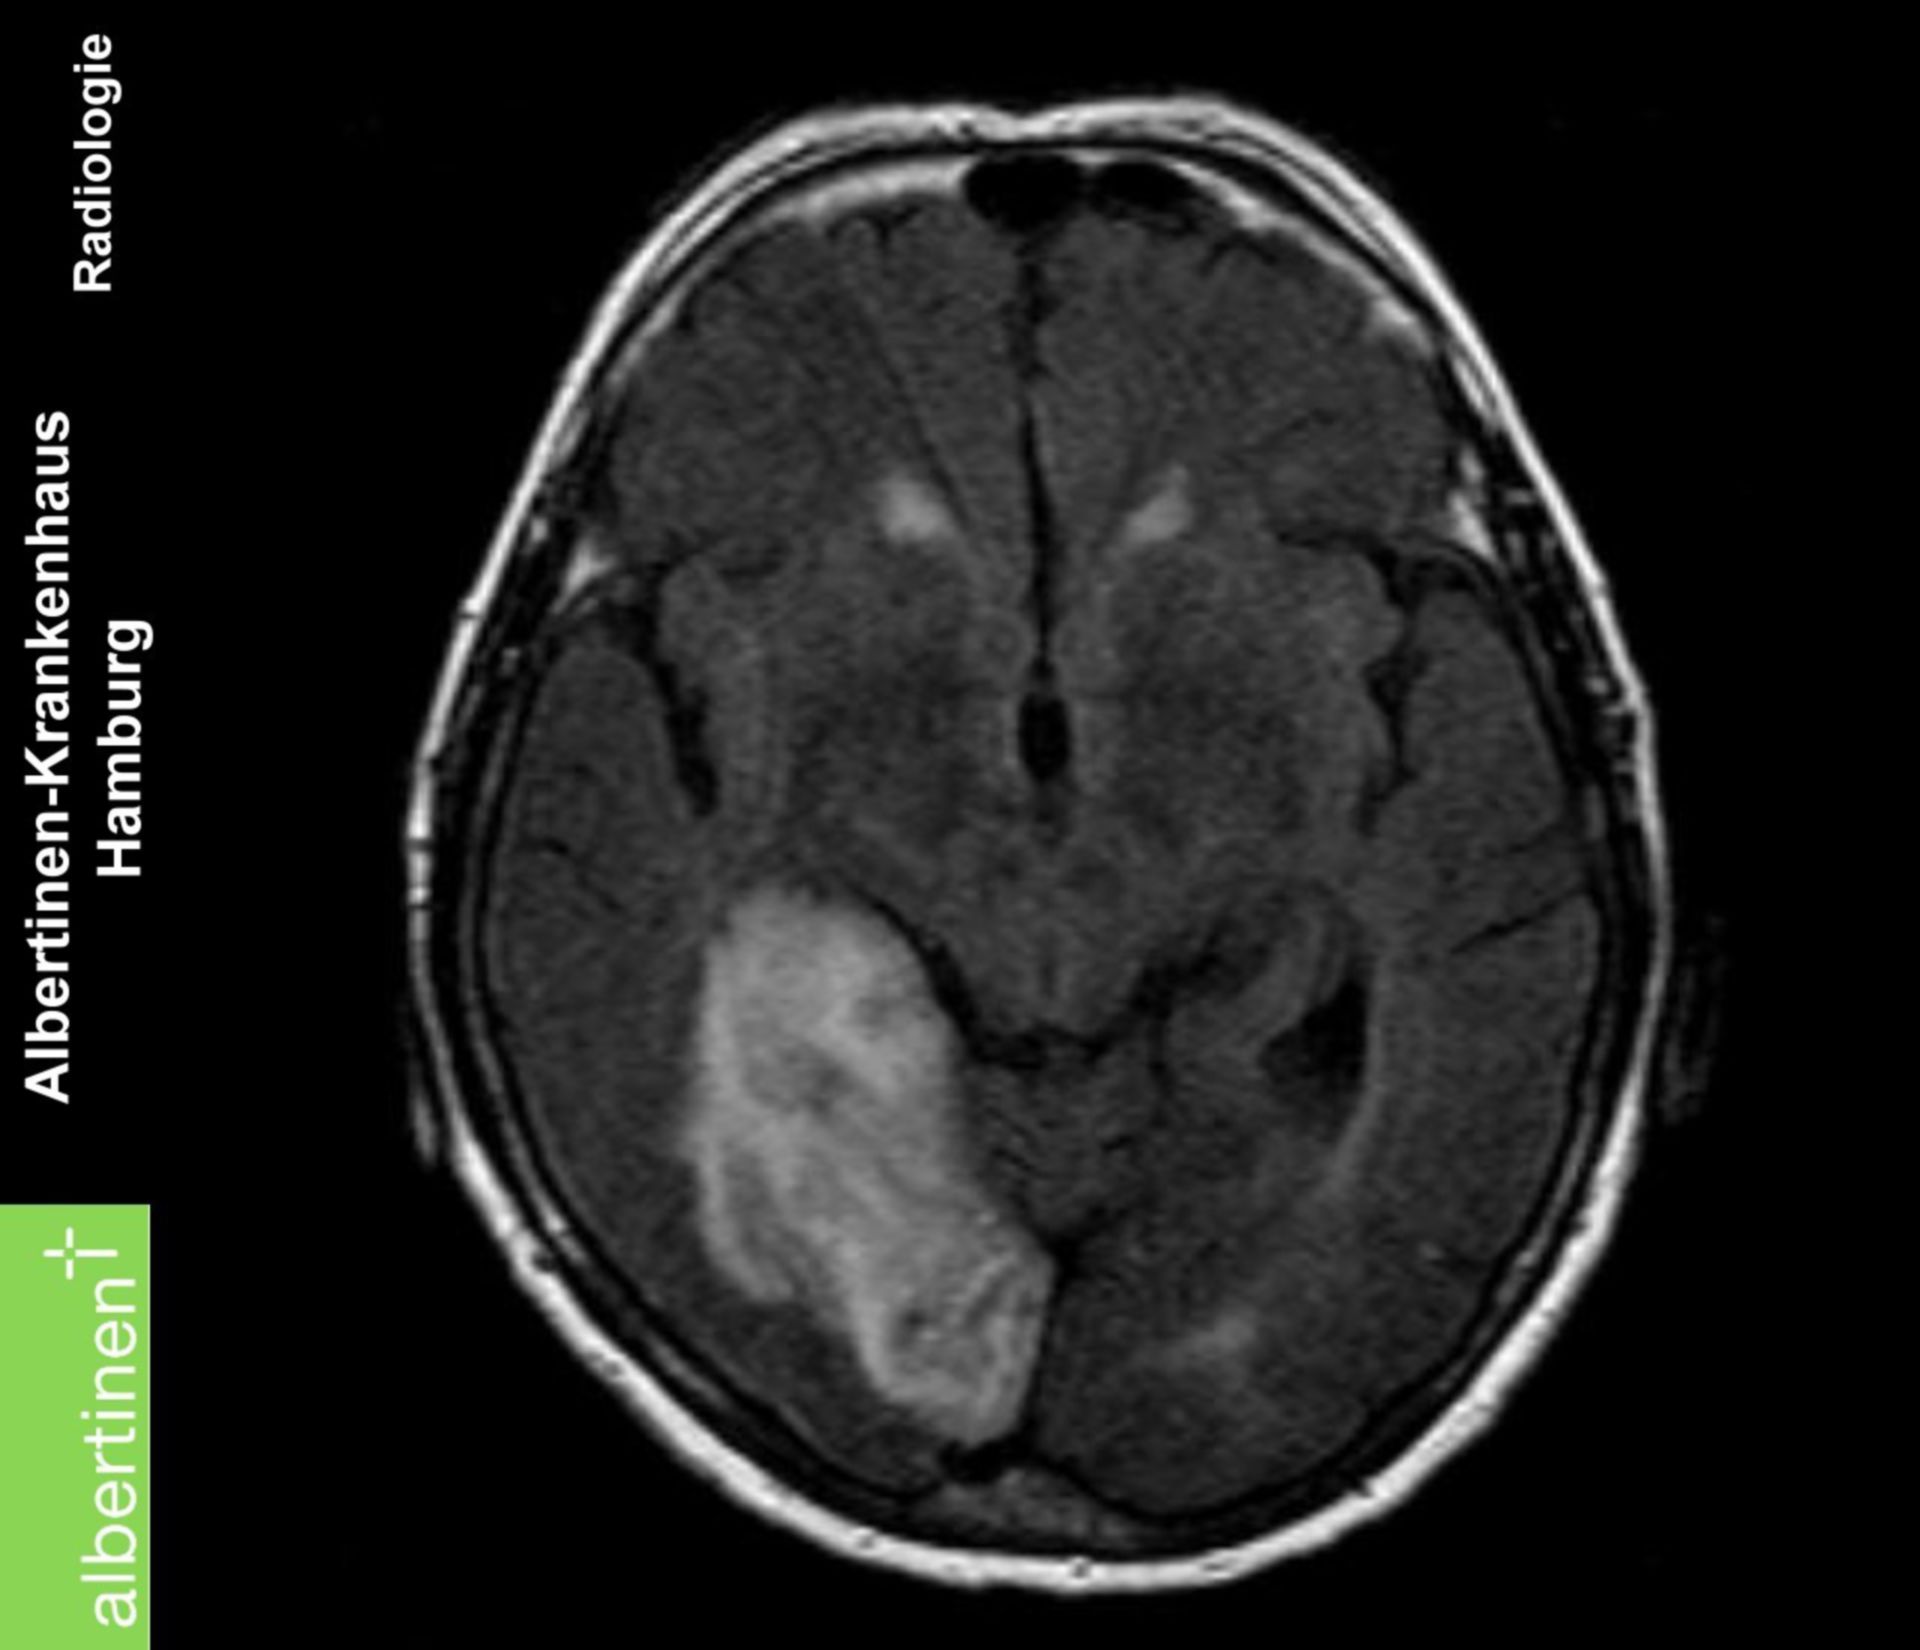

MRT Bild, könnte das ein Tumor sein? Kennt sich jemand damit aus? Könnte die helle Fläche ein … Myokarditis (MRT) – DocCheck

?wer kann helfen?ist in diesen MRT ein Tumor sichtbar? MRT abdomen – DocCheck

Glioblastom in der MRT,T1-gewichtet mit Kontrastmittel, sagitaler Schnitt aus dem KGU | Kampf … MRT eines Bandscheibenvorfalls an der LWS – Lizenzfreies Bild – #15202613 | Bildagentur PantherMedia

MRT: Posterior-Hirninfarkt – DocCheck Map Of Mrt Malaysia – Maps of the World

MRT Toxoplasmose – DocCheck Mrt Bilder – Meniskusriss? (Knie, Orthopädie, Chirurgie)